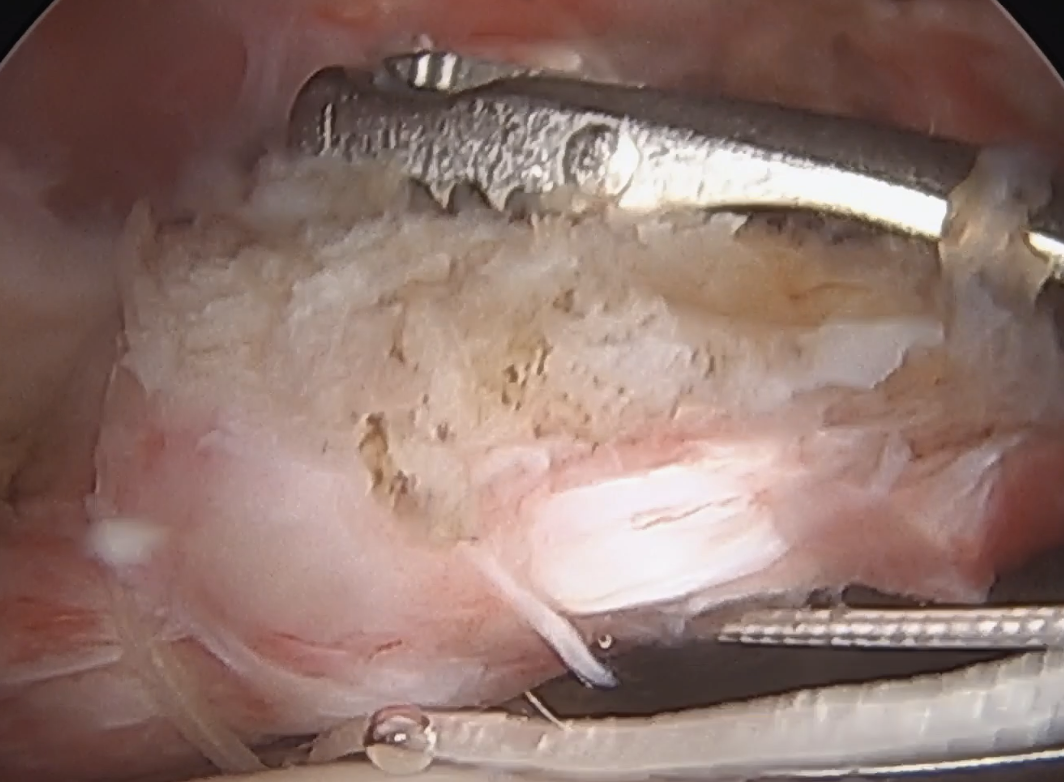

Lateral traction sutures placed in subscapularis, then cautery used to remove scar tissue and recreate rotator interval